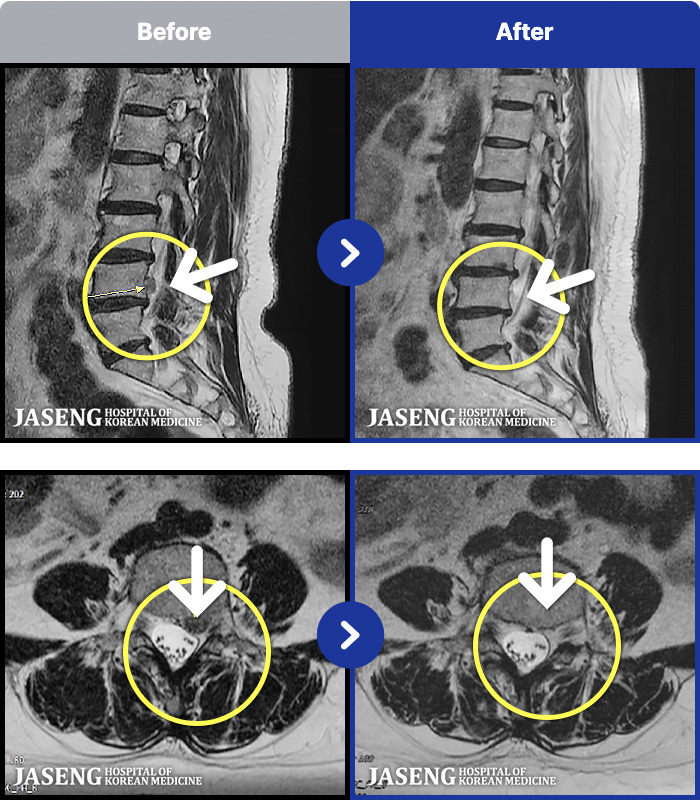

MRI ġ

1,237 MRI ũ ʸ Ȯϼ.

[Կñ:25.03.04~25.09.10]

[õ_㸮ũ] ߲ 㸮 , ٷ

No.1235

ȸ 139

2025.09.22